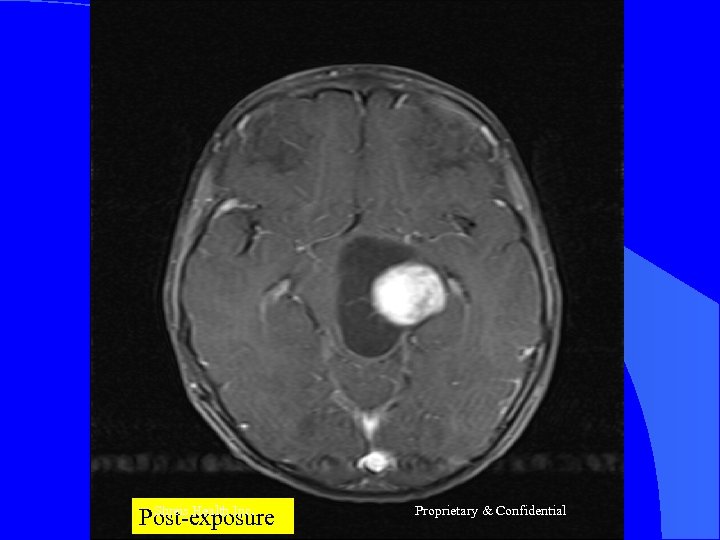

CASE 2 Mr R, 56 yrs l Nov 2004 – MRI Brain = Left frontal SOL (4 x 3 cm) - SX = Craniotomy x decompression of insular glioma HPR = Glioblastoma Grade IV l RT – 60 Gy/30 # till Jan 2005 l CT – Temedol x 2 # till Feb 2005 l Shreis Health Inc. Proprietary & Confidential

l l Presented Feb 05 - Loss of memory - Apathetic - Hemiparesis ® (power 3/5) Today after 1 course of RFQMR - No focal/Gen Neuro deficit - Normal higher functions and back to work. Shreis Health Inc. Proprietary & Confidential

Shreis Health Inc. Post-exposure Proprietary & Confidential

Shreis Health Post-exposure Inc. Proprietary & Confidential